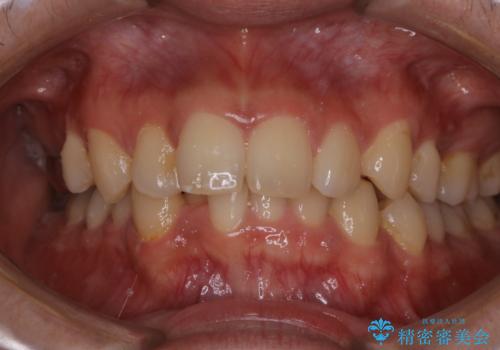

- 結婚式前にできる限りで白く、綺麗な歯にして欲しいとのことで来院されました。歯科は5.6年ぶりとのことでした。

PMTC

プラークが放置されると、そこで歯周病菌が繁殖し始めます。よって歯肉に炎症が生じ、歯周病に引き金となります。

PMTC(保険外治療)は、毎日の歯磨きで落としきれない汚れや、コーヒ、紅茶・タバコのヤニなどの着色も除去します。目には見えない歯と歯の間・歯肉の境目などに残っているプラーク(歯垢)もしっかり取り除きます。PMTCでは専門的な機械や材料を使用して、徹底的に汚れを除去するため、虫歯・歯周病・口臭予防などにつながります。

またPMTCを行うことで、ご自身本来の歯の色になり自然な明るさになります。

口元が自然な明るさになることで、より清潔感のある印象になるため結婚式・行事やイベント前などにもPMTCを行うはおすすめです。